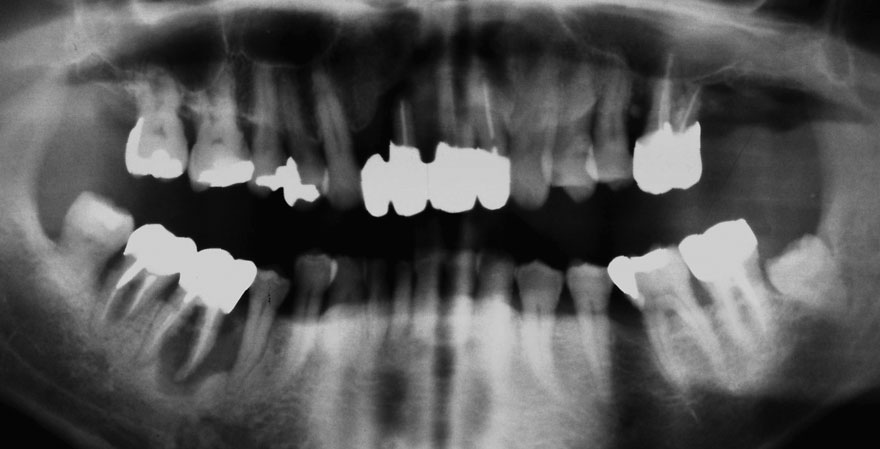

初診時 38歳 男性 平均歯槽骨喪失量:6.520mm

25年後 63歳

平均歯槽骨喪失量:8.57mm

25年間喪失量:-2.05mm

年間喪失速度:-0.08mm

(ケア頻度:1.38ヵ月ごと)